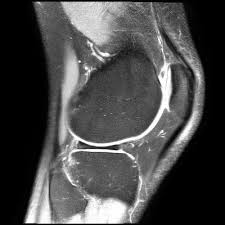

Такая травма тяжело поддается диагностике. По внешним признакам она схожа с другими травматическими повреждениями. А на рентгеновских снимках, которые обычно делают после получения травмы, мениски просто не просматриваются. Опытные травматологи начинают обследование со специальных двигательных тестов, которые подскажут о наличии отклонений.

Чтобы уточнить диагноз, могут назначаться обследования в виде:

- МРТ. Метод высокотехнологичный и точный. Благодаря трехмерному сканированию отображаются все изменения, произошедшие с менисками. Но, к сожалению, томография доступна не всем пациентам из-за своей высокой стоимости.

Сколько степеней повреждения мениска?

В настоящее время выделяют 4 степени разрыва мениска: 1-я, 2-я, 3а и 3б. И именно для определения стадии травматологи-ортопеды, как правило, и назначают МРТ диагностику коленного сустава.